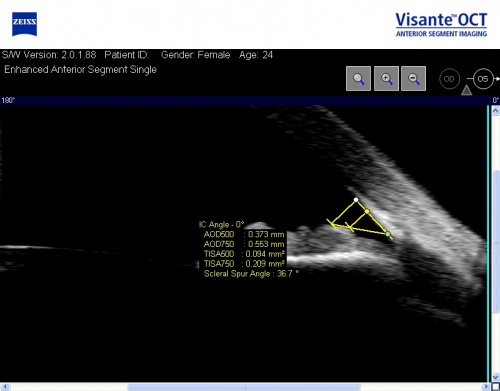

The Visante OCT has several scanning protocols of which the Enhanced Anterior Segment Single Scan and the High Resolution Raw scan are most useful for angle assessment. Figure 1 is an example of a good-quality Enhanced Anterior Segment Scan. The important features include good horizontal and vertical centration of the image within the frame, the presence of a reflex saturation beam indicating perpendicularity of the eye to the scanning beam and minimal tilting of the image. The scan dimensions are 16 x 6 mm and 4 image frames are averaged in order to increase the signal to noise ratio. In this scan protocol, the image is automatically corrected for the effects of refraction of the scanning beam. The High Resolution Raw Scan samples 512 A scans/image (as opposed to 256 A scans/image for the Enhanced scan), there is no image averaging or refraction correction.

The commonly used quantitative parameters are as follows (Figure 3):

- Angle opening distance (in mm): Perpendicular distance between a point 500µm (AOD 500) or 750 µm (AOD750) anterior to the scleral spur and the opposing iris.

- Angle recess area (in mm2): The triangular area (ARA 500 or 750) bounded by the AOD 500 or 750, the anterior iris surface and the inner corneo-scleral wall

- Trabecular space area (in mm2): Trapezoidal area (TISA 500 or 750) bounded by the AOD 500 or 750, the anterior iris surface, the inner corneo-scleral wall and the perpendicular distance between the scleral spur and the opposing iris.